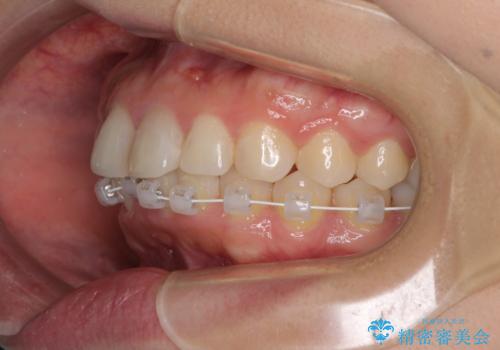

矯正治療の後戻り ガタガタになった前歯の部分矯正

- 以前の矯正治療の後戻りを気にして来院された患者様です。

下顎前歯にデコボコがあるため、ワイヤー矯正により改善することとしました。

もう少しデコボコを改善したかったのですが、ご本人の希望もあり、装置を除去しました。

後戻りを防止するため、舌側を細いワイヤーによる保定を行いました。